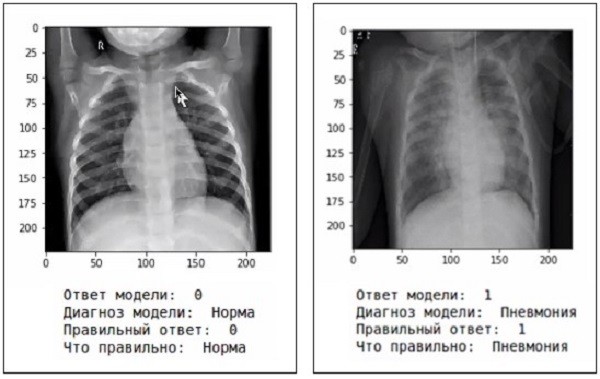

Напомним, учеными опорного вуза Марий Эл - Марийского госуниверситета - запущен проект, направленный на поиск аномалий в рентгеновских снимках при помощи искусственного интеллекта. Сейчас, благодаря научным разработкам, можно определить коронавирусную пневмонию с точностью 98%.

Сейчас марийские ученые продолжают работать над проектом. Они планируют «обучить» нейронные сети определять вирусную и бактериологическую пневмонии.